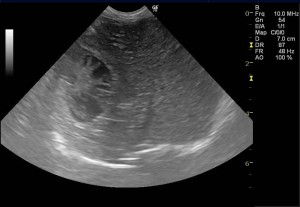

以前より胆嚢内の粘液腫様変性が認められていたため注意して経過観察を実施していた症例です。超音波では、胆嚢の拡張は認められないものの、内部の変性(キウイフルーツ様パターン)は顕著に認められました。

診断:胆嚢粘液嚢腫